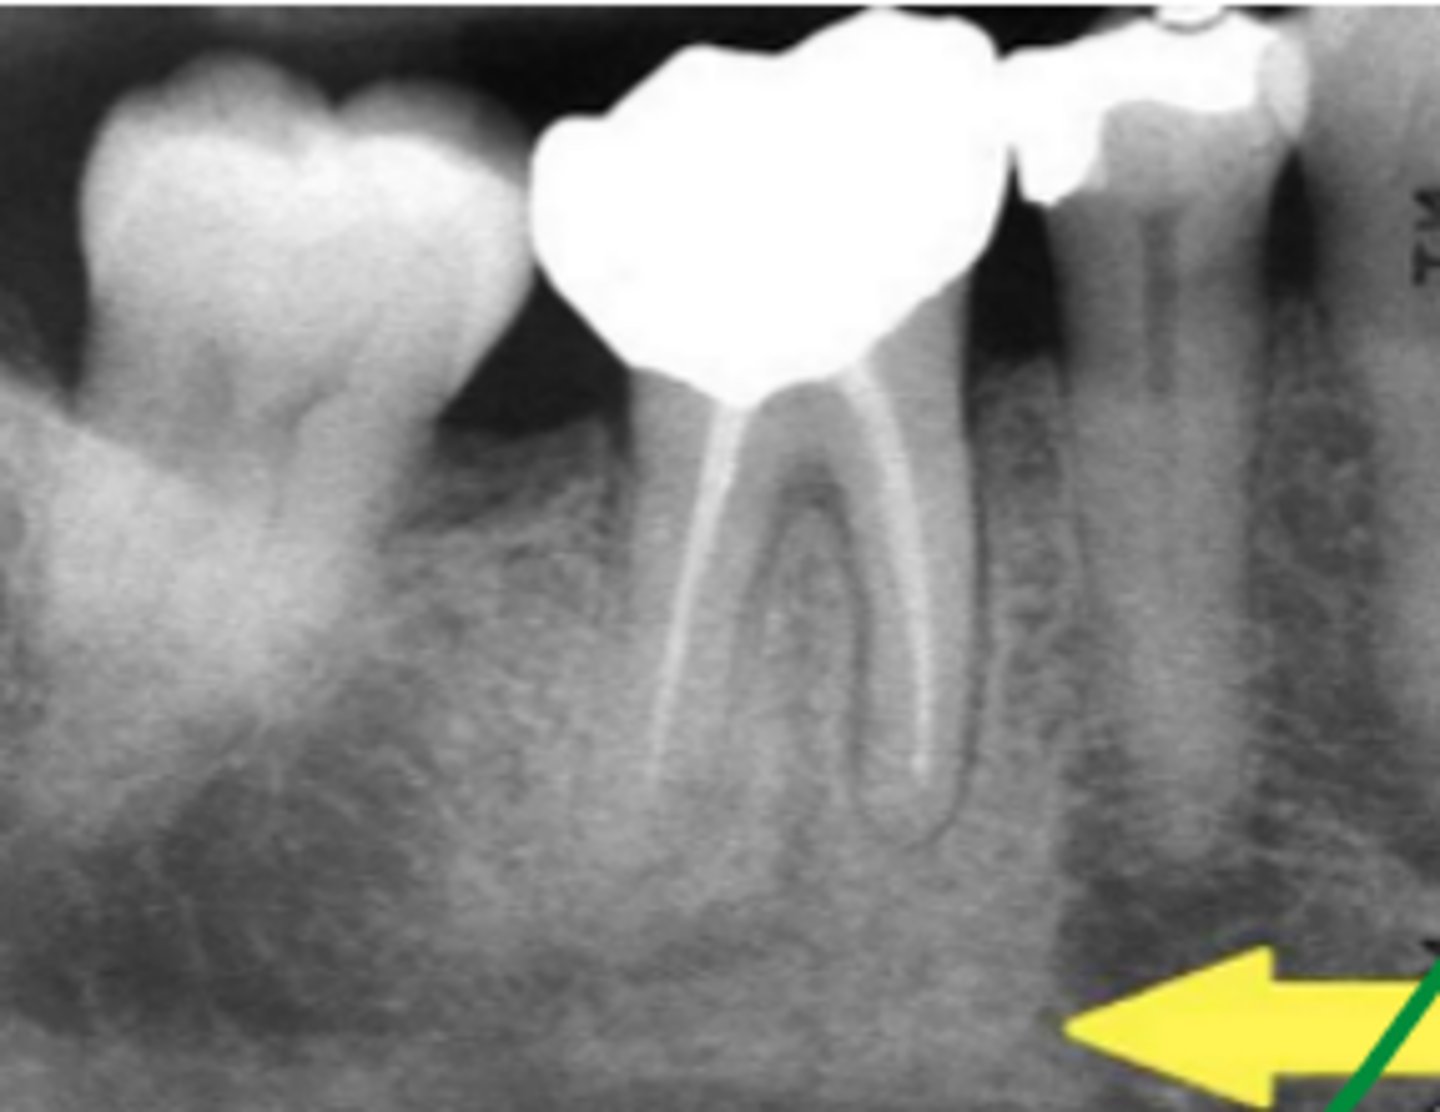

What is Periapical Sclerosing Osteitis also known as?

Condensing osteitis

What does Periapical Sclerosing Osteitis indicate?

Long standing infection